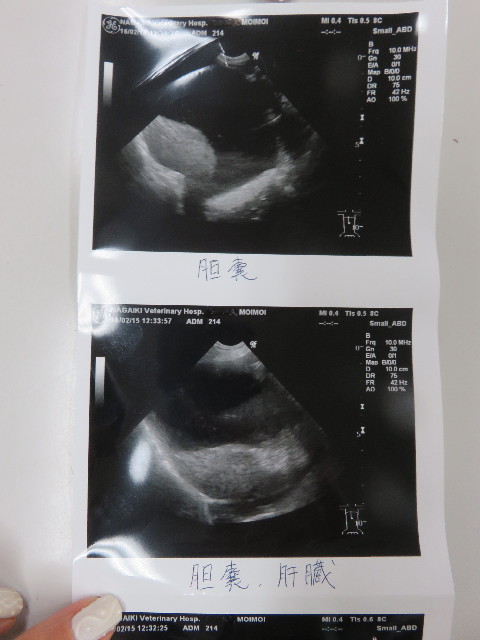

それってどうなの?肝臓さんは大丈夫なの?と思い先生にちょっときいてみました。

●肝臓への負担は、血液検査をマメにしていていつも問題がないのでそんなに心配しなくて大丈夫と思う。とのこと。